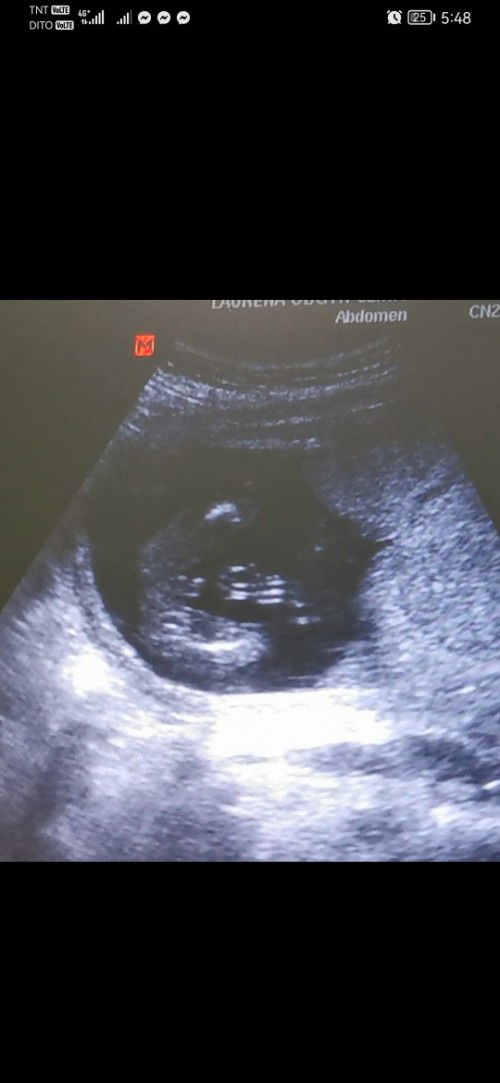

Is it a boy or girl? Mga momsh, baka may mga marunong po magtingin? Thanks you.

parang boy po ganyan din po position ng akin ihh

parang boy mii